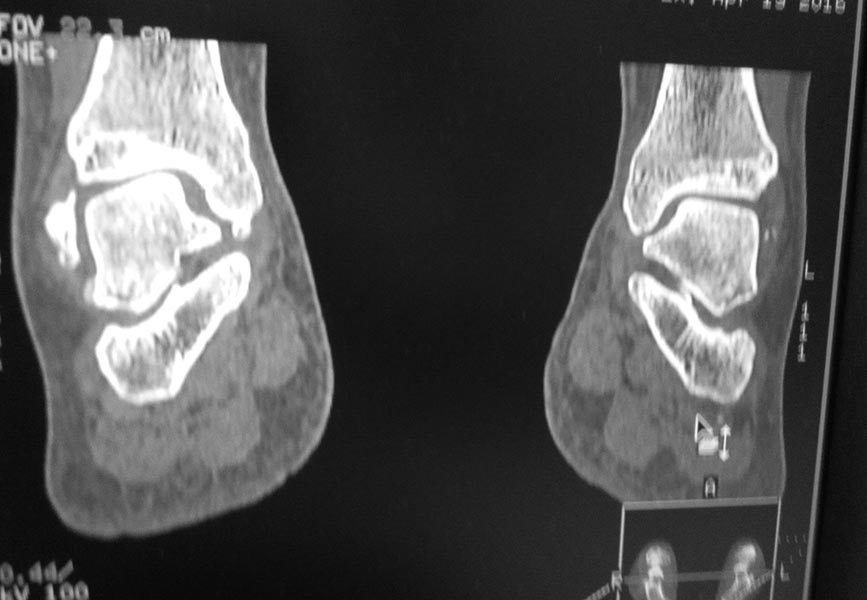

Обратилась женщина 1975 г.р. Жалобы на боль в голеностопном суставе при нагрузке (после ходьбы на расстояние 200 метров).

Травма три года назад. Упала с высоты своего роста, подвернула ногу, лечилась амбулаторно с Ds : растяжение связок голеностопного сустава. Rg не делали. После травмы боль осталась, в динамике интенсивность боли прогрессировала. Ухудшение в течении последних 6 мес. Местно : движения в голеностопном суставе в полном обьеме, отек незначительный. Пальпация безболезненна.Rg, Кт прилагается.

Какова на ваш взгляд тактика лечения в данном случае?